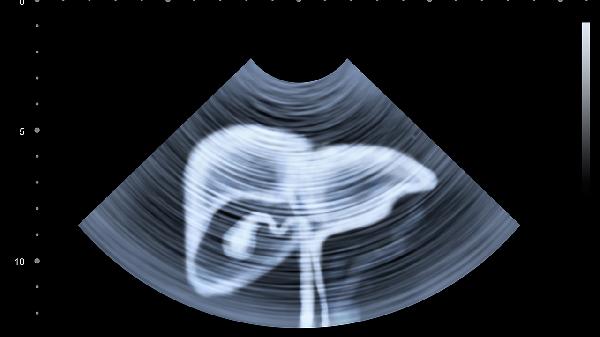

建議每年進行肝功能檢查和肝臟超聲篩查,乙肝表面抗原陽性者需每3-6個月復(fù)查。40歲以上人群應(yīng)增加肝臟彈性檢測,有肝癌家族史者需進行甲胎蛋白監(jiān)測。發(fā)現(xiàn)轉(zhuǎn)氨酶異常升高或占位性病變應(yīng)及時??凭驮\。